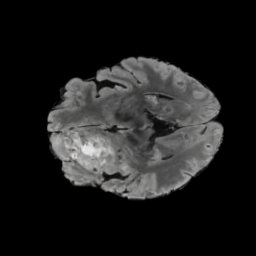

Our results unequivocally highlight the superior performance of X-Diffusion in terms of both qualitative and quantitative metrics. Representative MRI volumes generated by our pipeline, when juxtaposed with ground-truth images, showcased remarkable similarity, with even intricate physiological features like tumor information, spine curvature, and fat distribution being accurately captured.

Notably, X-Diffusion achieves sota dB for a few input slices while baselines require more than 60 input slices to achieve similar performance (Figure 7). The margin is more than 12 dB PSNR for the 1-slice input in both the BRATS and the UK Biobank benchmarks (see Table 1 and Figure 6). For reference, two randomly sampled MRIs from the UK Biobank would have a PSNR of 15.95 dB 0.36 (on 4800 randomly sampled examples). The slices from 3D reconstructed volumes at varying depths and axis of rotation visually match the ground truths (see Figures 5 and Figure 4). We also plot the error map (Figure 4) of such X-Diffusion generations to highlight the differences with the ground truth MRIs.

Tumour Information Preservation. For the brain tumor segmentation, we use a Swin UNETR model[27, 70], trained with random rotation, and intensity as data augmentation. In Figure 5, we highlight the tumor profiles of the generated MRIs compared to the ground truth tumour profile. In the test set with human ground-truth annotations (), the real MRI Dice score is 85.15 while the generated MRIs from a single slice have a dice score of 83.09. This shows how the generated MRIs indeed preserve the tumor information and can act as an affordable and informative pseudo-MRI, before conducting an actual costly MRI examination in hospitals.